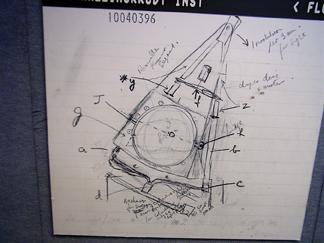

The Radiological Society of North America (RSNA) will officially kick off its 100th annual meeting and scientific assembly (Nov. 30 – Dec. 5, McCormick Place, Chicago) with a look back on the role RSNA has played in the history of radiology, brought to life in the RSNA Centennial Showcase.